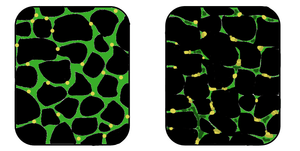

|

In affected muscle (right), the tissue has become disorganized and the concentration of dystrophin (green) is greatly reduced, compared to normal muscle (left). | |